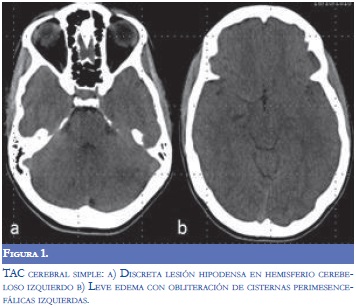

Debido al cambio agudo del estado de conciencia y los hallazgos sugestivos de lesión en el tallo cerebral, se practicó de forma urgente tomografía simple de cráneo la cual demostró signos leves de edema cerebral y escasas hipodensidades en el hemisferio cerebeloso izquierdo (Figura 1). Además, se efectuó hemograma que evidenció leucocitosis con neutrofilia, sin anemia ni trombocitopenia y química sanguínea dentro de parámetros normales. Con la sospecha clínica de romboencefalitis infecciosa se inició cubrimiento antimicrobiano con ceftriaxona, ampicilina, aciclovir y dexametasona. Posteriormente, se realizó punción lumbar y se encontró presión de apertura de 6 cmH20 con citoquímico normal (leucocitos 0, Proteínas: 33 Glucorraquia 63/93) con coloración Gram y antígenos bacterianos negativos, y días posteriores al procedimiento se obtuvieron los resultados del cultivo y la PCR para los virus de la familia del Herpes todos negativos.

Los hallazgos paraclínicos incluyen leucocitosis, elevación de la VSG y PCR, y pleocitosis e hiperproteinorraquia en el líquido cefalorraquídeo (9,11,12). Con respecto a las imágenes diagnósticas, la tomografía de cráneo puede ser normal o demostrar alteraciones inespecíficas (5). La resonancia magnética cerebral demuestra hiperintensidades multifocales bilaterales irregulares en las secuencias con información T2 y FLAIR, hallazgos sugestivos de edema cerebral extenso y áreas de hemorragias puntiformes demostradas en las imágenes de susceptibilidad magnética. Estos últimos hallazgos son útiles en el diagnóstico diferencial dado que no suelen encontrarse en ADEM (13). El compromiso se localiza característicamente en la cápsula interna, el tallo cerebral, el cuerpo calloso, el lóbulo parietal y el cerebelo (6,11).